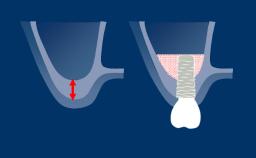

- recognize the anatomic characteristics of the peri-implant soft tissues in health

- identify the effects of inflammation on the peri-implant soft tissues